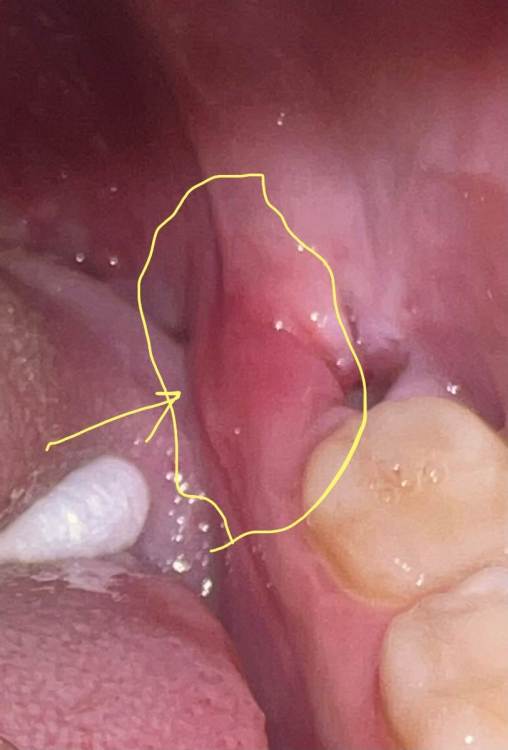

JeanneK Опубликовано 13 июля, 2023 Автор Поделиться Опубликовано 13 июля, 2023 (изменено) Добрый вечер! Лунка потихоньку зарастает, но достаточно сильно болит десна в указанном месте. Там как бы небольшой беловатый выступ. Не острый. Это экзостоз, который надо убирать или все само зарастет десной? upd. К сожалению, к врачу раньше понедельника попасть не смогу ( Изменено 13 июля, 2023 пользователем JeanneK Ссылка на комментарий

IvanK Опубликовано 14 июля, 2023 Поделиться Опубликовано 14 июля, 2023 Добрый день скорее всего острый край лунки, к сожалению так бывает если беспокоит, то нужно "сгладить", если не очень - то можно подождать Ссылка на комментарий

JeanneK Опубликовано 20 июля, 2023 Автор Поделиться Опубликовано 20 июля, 2023 Добрый день. Так я задавала. Говорит все в порядке. Все в норме. Сказал закладывать метрогил. Но если будет болеть, вероятно, нужно будет подпиливать десну после эпителизации лунки. Правда острого края там нет, а в месте отека, который я обвела, скорее микроэкзостозы, гребень (?), у меня и с другой стороны такой. На форум прихожу как раз потому, что от врача нет нормального ответа, только ждать... я боюсь прошляпить что-то неприятное, пока жду Ссылка на комментарий

JeanneK Опубликовано 20 июля, 2023 Автор Поделиться Опубликовано 20 июля, 2023 Да в том-то и дело, что нет там острого края, на мой взгляд. А вы его видите? Сколько еще может держаться краснота и отек десны? Ссылка на комментарий